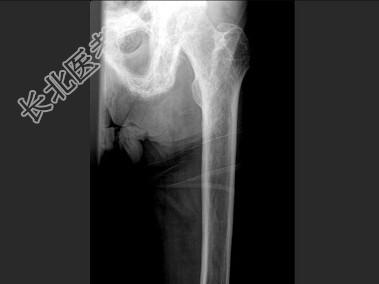

- 单项选择题男,60岁, 左股骨痛1年余,结合图像, 最可能的诊断是 ( )

A、骨纤维异常增殖症

B、Paget病

C、髋关节结核

D、股骨头缺血坏死

E、化脓性骨髓炎